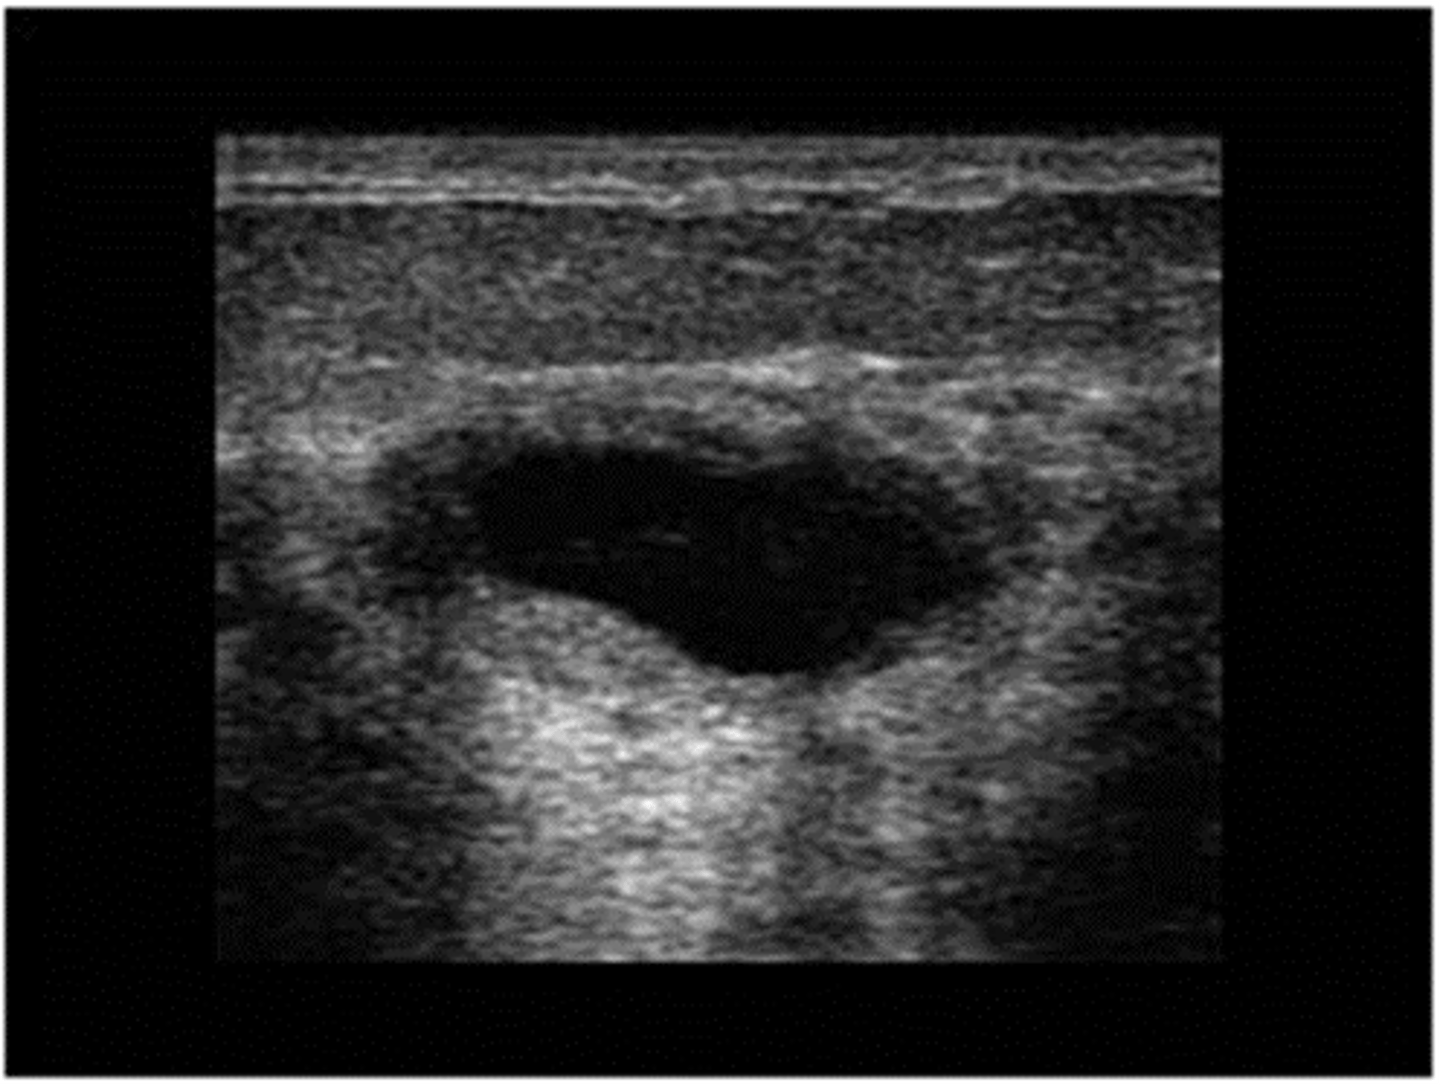

cyst

30-50 yo

Regress after menopause

Single or multiple

Round

Soft/firm, rubbery

Well -demarcated

Mobile

Often tender